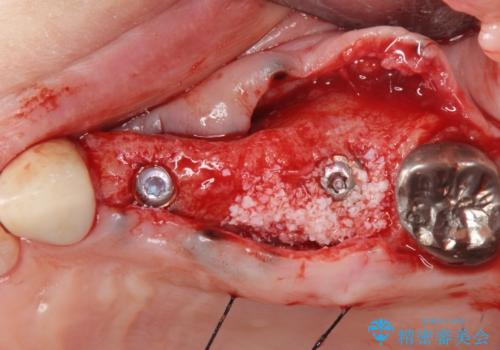

- 歯のないまま放置していた左上奥歯の咬合機能回復を求めて来院されました

咬合力が強く、入れ歯では周囲の歯も欠損状態になることが予想されたので、しっかりと咬合機能の回復のできる

インプラント治療を行うこととしました。

インプラント2本で3本分の咬合機能を回復することができました。(インプラントブリッジ治療)